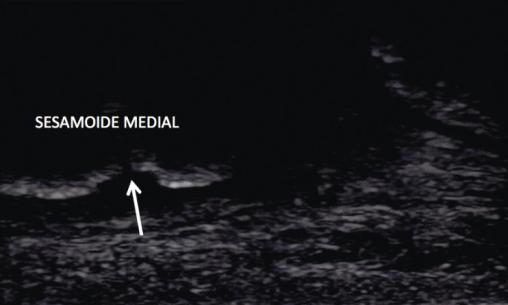

L’échographie décèle une effraction de la corticale du sésamoïde médial, confirmant le diagnostic de fracture de fatigue (fig. 2 ).

L’échographie décèle une effraction de la corticale du sésamoïde médial, confirmant le diagnostic de fracture de fatigue (

L’échographie, réalisée par un opérateur expérimenté, met en évidence une fragmentation de la corticale osseuse.